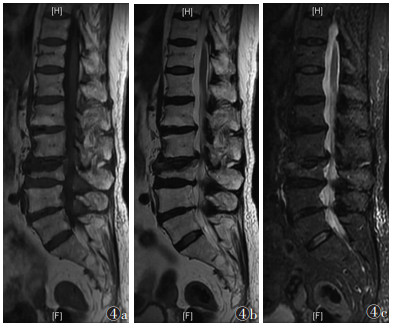

168节椎体中,轻度骨髓水肿32节,中度70节,重度66节。随时间推移,骨髓水肿信号强度逐渐由均匀向非均匀转变,信号范围逐渐减小,边界逐渐清晰;轻度骨髓水肿发生率由8.4%升至50.0%,重度由51.8%降至8.3%,差异均有统计学意义(均P<0.050.05)(表 3)。①Ⅰ期:骨髓水肿比例迅速上升,达到峰值。T1WI、T2WI信号均匀分布,T1WI呈低信号,T2WI和STIR呈高信号,扩散至正常骨髓,呈弥漫性、均匀性、边界不清的形态分布(图 1)。②Ⅱ期:信号分布变得不均匀,水肿范围逐渐受限,并出现点、片状T1WI低信号,T2WI和STIR高信号(图 2)。③Ⅲ期:骨髓水肿较前一期下降,水肿范围局限于骨折区,信号混杂;部分椎体T1WI呈等、低信号,T2WI及STIR呈低、等、高信号(图 3)。④Ⅳ期:骨髓水肿百分比降至最低。T1WI骨折区可见低信号区,边界清晰。T2WI和STIR信号与相邻正常椎体相同(图 4)。

| 图 4 女,77岁,Ⅳ期OVCFs。MRI示骨折位于L3,T1WI(图 4a)呈低信号,T2WI(图 4b)及STIR(图 4c)呈等或稍高信号,边界清晰 |